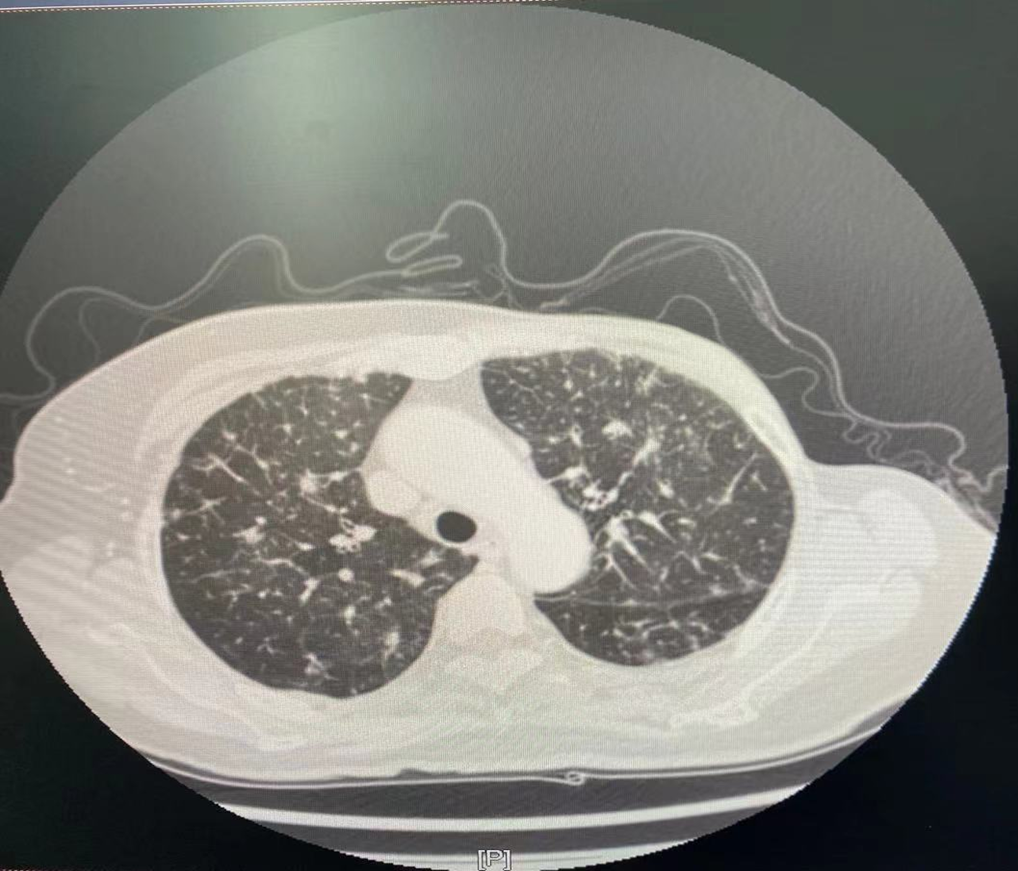

图3.骨扫描

2021年4月7日骨扫描:全身多发骨质代谢异常,考虑多发骨转移。